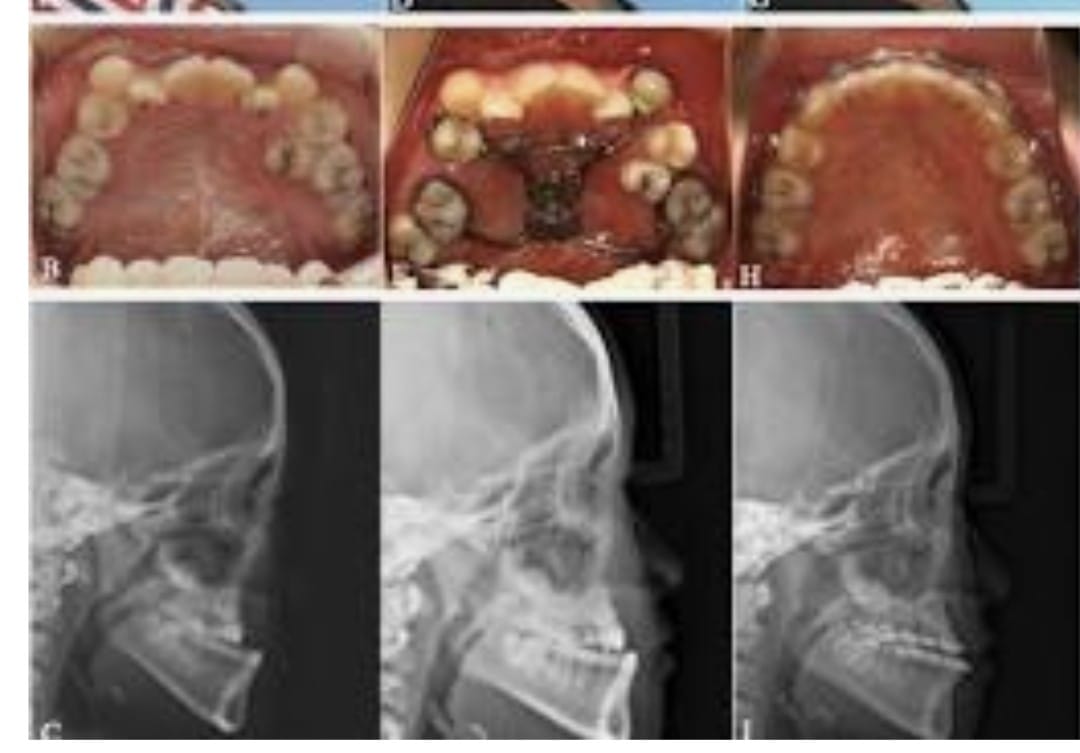

Orthognathic surgery focuses on correcting jaw misalignments and improving the function and appearance of the face through advanced surgical techniques. Whether it is correcting jaw deformities, restoring facial harmony, or reversing signs of aging, orthognathic surgery helps patients achieve natural-looking results while maintaining their unique facial features.